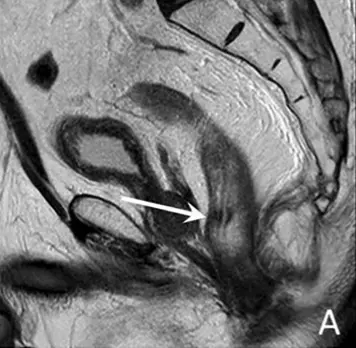

In a multireader study comparing 4 MRI methods for rectal tumor response evaluation, those incorporating DWI showed the best results when combining diagnostic performance, IOA, and reader preference. The most preferred method (by 73% of readers) was the “DWI patterns” approach with an accuracy of 68%, high specificity of 82%, and group IOA of 0.43. Reader experience level and MRI quality had an evident effect on diagnostic performance and IOA.